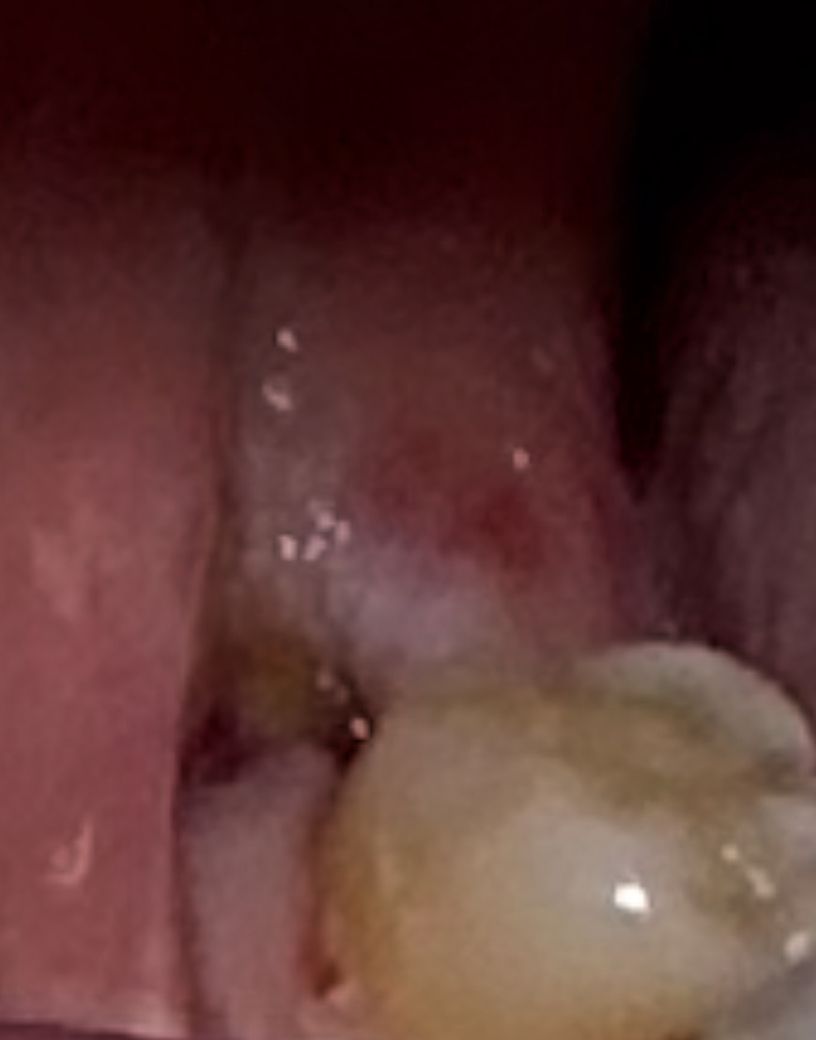

사랑니 발치후 잇몸 구멍이 났습니다.

사랑니 발치후 72시간째입니다.

발치 자리에 잇몸이 70%가량 새로 덮어진 상태(사진의 빨간영역)이고,

사진의 노란색 자리는 구멍이 보이고 있습니다.

발치 후 실밥도 꼬매지를 않으신 상태라

현재 정상적으로 아무는 과정이라고 볼수 있는건지요?

• 1번 째 사진

사진상으로 발치한곳은 잘 아물고 잇는거 같습니다. 잇몸이 치유되는 과정주엥 생기는 자연스러운 현상이니 너무 걱정하지마세요.

염증의 소견은 보이지 않습니다. 정상적으로 잘 낫고 있어보이니 며칠정도 관리잘해주시면 됩니다.

발치 후 3일째의 적절한 치유 양상을 보여주고 있습니다 걱정마시고 발치 후 주의사항 잘 지키세요

이정도면 정상적으로 아물고 있는 것으로 보입니다. 시간이 지나면 점점 살이 차오르게 됩니다. 건드리지 말고 그냥두면 됩니다.

사랑니를 발치하고 나면 발치한 부위에 구멍이 날수 있습니다. 이런 부분은 시간이 지나면서 점차 차오르게 됩니다. 발치한부위에 이물질이 들어가게 되면 가볍게 가글을 해주는 것이 좋습니다.

억지로 제거를 하려고 하지 않는것이 좋습니다.